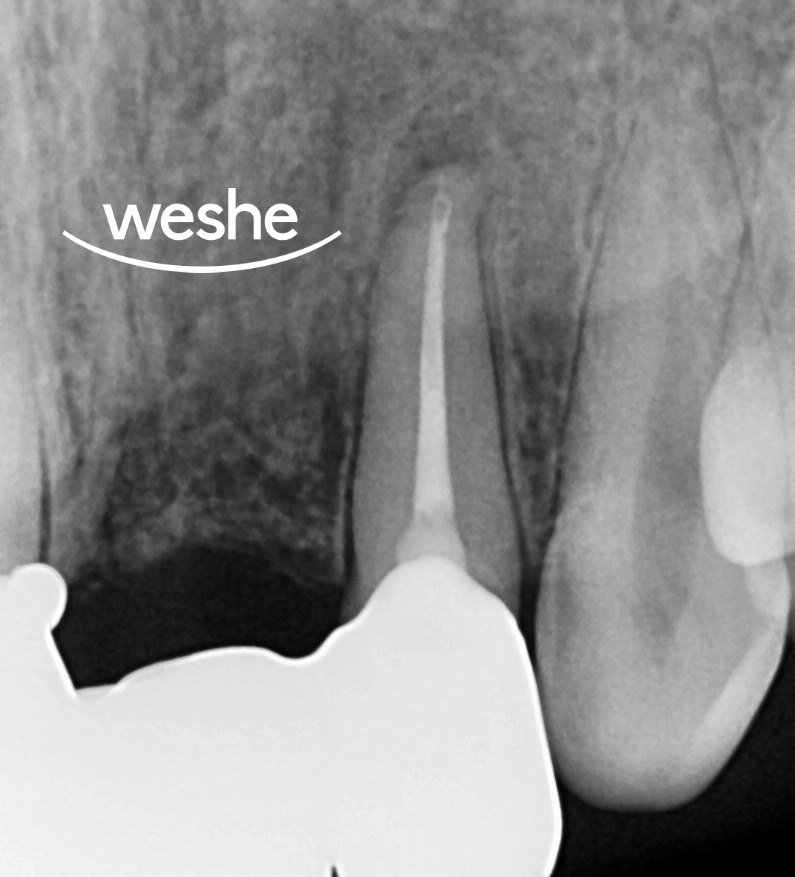

20250819

안정화가 충분히 이루어지면

최종 브릿지 제작을 위한

치아 형성을 진행합니다.

정출된 #22번 치아는 이제

잇몸 위로 충분한 치질이 드러나게 되어

보철 제작을 위한

이상적인 조건을 갖추게 됩니다.

11번 치아도 함께 형성하여

새로운 브릿지를 제작합니다.

디지털 인상 채득을 통해

정밀하게 제작이 가능합니다.

약 10주에 걸친 치료 과정을 통해

발치 없이 자연치를 보존할 수 있습니다.